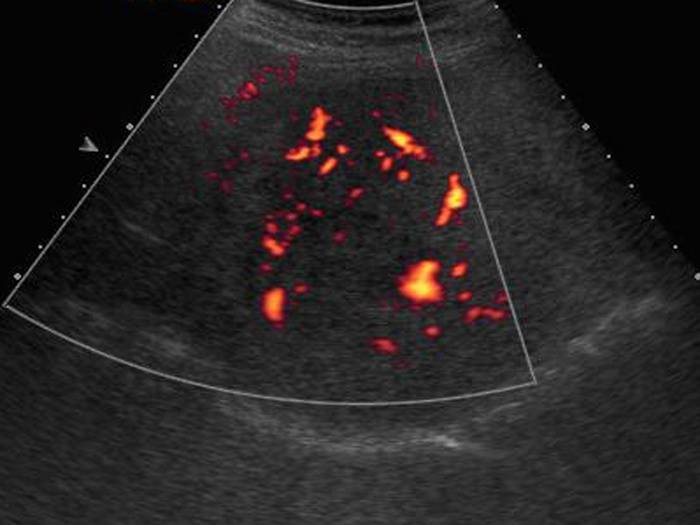

Sán lá gan

» Thông tin: Nam giới – 52 tuổi.

» Lâm sàng: Kiểm tra sức khỏe.